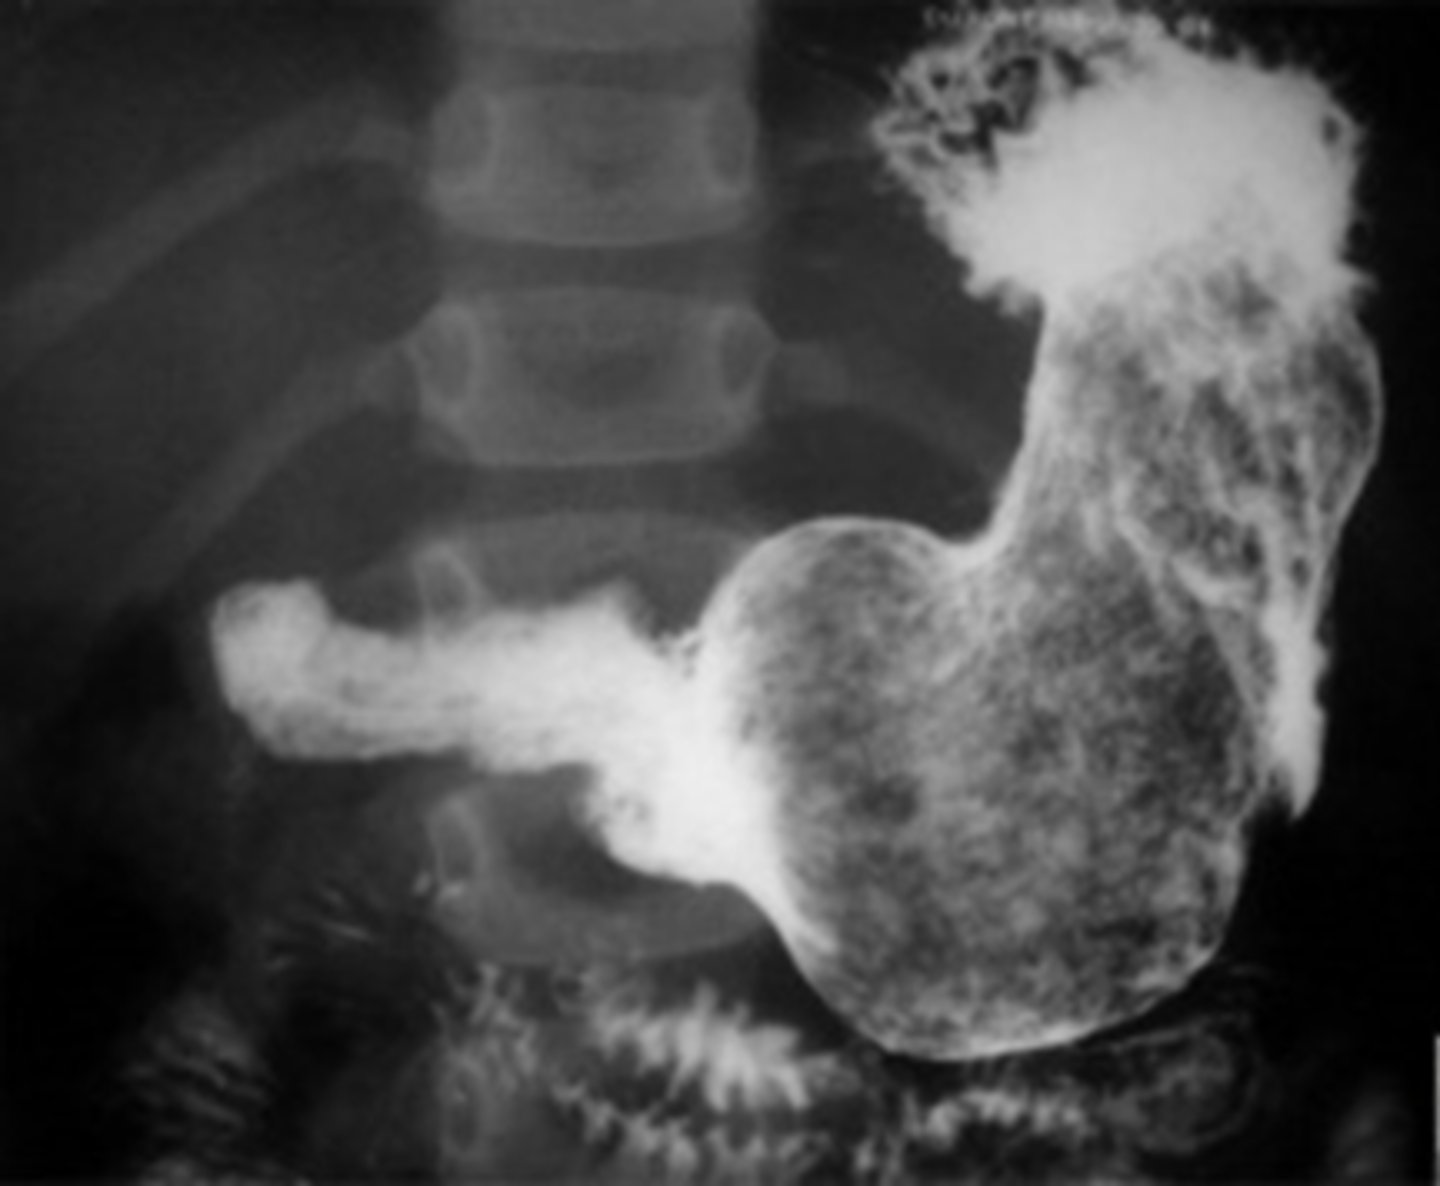

What is best initial & best overall test to diagnose hypertrophic pyloric stenosis? What will be seen?

Initial: abdominal US

Best: upper GI contrast series - string/apple core sign